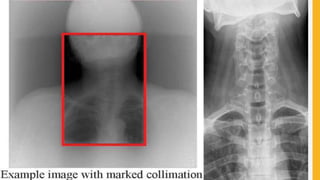

COMPARISON OF RADIOGRAPHIC IMAGES

Image without Image with

Scattered radiation Scattered radiation

COMPARISON OF RADIOGRAPHICIMAGES Image without Image with Scattered radiation Scattered radiation